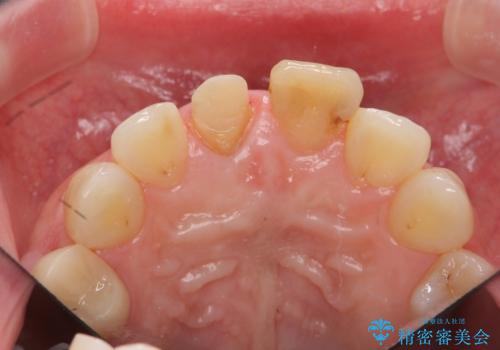

リアルな歯の色調にこだわるオールセラミッククラウン治療

- 歯の神経を除去したのちの、変色の改善を希望され来院されました。

再度根管治療を行ったのちの、オールセラミッククラン治療を計画します。

色調の再現に優れるオールセラミッククラウン スペシャルプランでの治療を希望されました。(保証5年間)

天然歯を再現したリアルな仕上がりに満足いただくことができました。

オールセラミッククラウン スペシャルプランは細やかな色調の再現に優れ、目立つ前歯の審美的な仕上がりがより達成されやすいプランです。